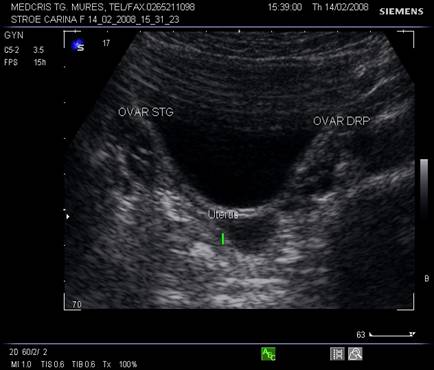

Fig. nr.349. Sectiune transversala prin pelvisul feminin , la ecografia abdominala postmenarcha, se remarca ovarele cu zone anecogene foliculare.

Fig. nr. 350.Uter infantil la o pacienta cu mozaicism Turner ( lungimea colului egala cu cea a corpului uterin ) la ecografia abdominala in sectiune sagitala